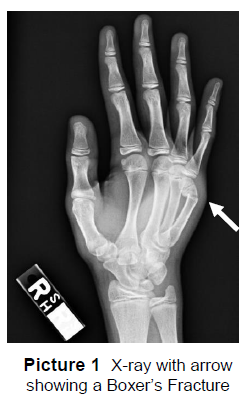

X-rays of the hand are taken to see if there is a fracture. A boxer’s fracture is a small finger metacarpal neck fracture (Picture 1).